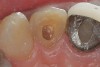

Figure 3  A radiograph will indicate whether the dark color is related to materials remaining in the pulp chamber, leaking restorations, caries, internal resorption, or failed endodontic therapy.

Figure 3